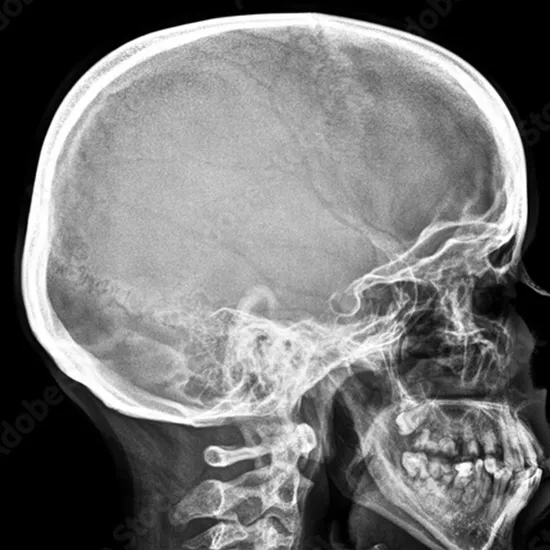

What is an X-ray Soft Tissue Neck (STN) Ap/Lat View Test?

An X-ray of the STN helps to view the airway structures as a whole. This examination evaluates the epiglottis, glottis, and subglottis, the three areas of the pharynx (which link the mouth and nose to the food pipe).